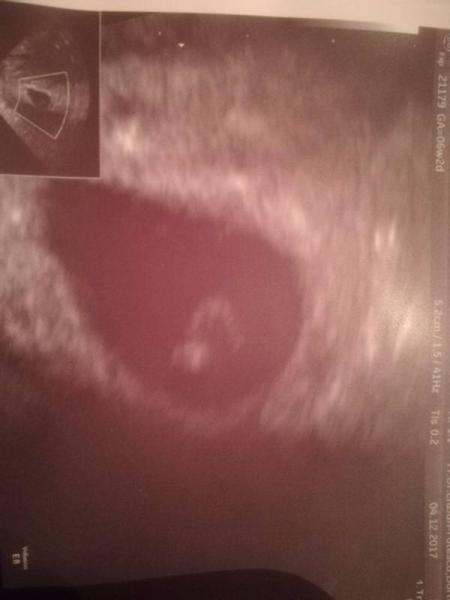

Hallo ihr lieben, meinen positiven Test vor einer Zeit hatte ich ja schon gepostet.Heute war mein erster FÄ Termin..Mein Böhnchen ist 3mm gross und das Herz hat schon geschlagen ..Ich bin grade so happy, hatte ich doch letztes Jahr am 20.12 einen MA in der 11ten Woche. Da saß ich auch im Juli Bus. Ausgerechnet bin ich für den 29.07.18..Bin somit heute bei 6+1. Ich bin übrigens 40 Jahre alt und habe einen Sohn von 18. J. Für meinen Ehemann ist es das erste Kind.Wir mussten lange dafür üben und geklappt hat es mit Hilfe der Kinderwunschklinik..Jetzt heißt es weiter hoffen! Lg, Naddel.

Herzlichen Glückwunsch Es ist so schön dass kleine Herzilein schlagen zu sehen nicht wahr?

Jaaaaaa unbeschreiblich